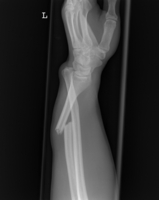

Unterarm

Monteggia-Fraktur

Galeazzi-Fraktur